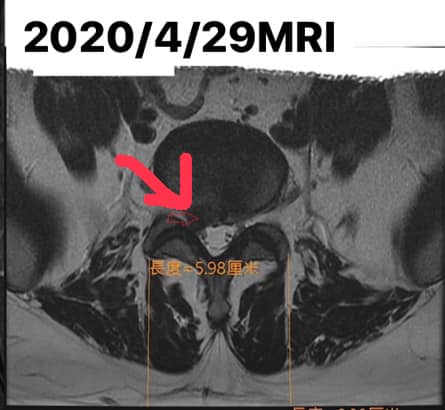

從事便當店的吳先生抱怨1年前搬東西受傷 ,從那個時候就開始痛,到今年4月嚴重疼痛,痛到他去醫學中心拍攝MRI,證實腰椎L5S1右側嚴重突出,在當地復健診所做了整整2個月的電療跟拉腰,狀況時好時壞,來診前已經痛到走路非常劇痛,只有躺下來才比較舒緩,每天早上都必須吃止痛藥 ,但還是壓不下來,疼痛指數超過八分

1.椎間盤突出右側L5S1 壓迫

2.小關節面紊亂